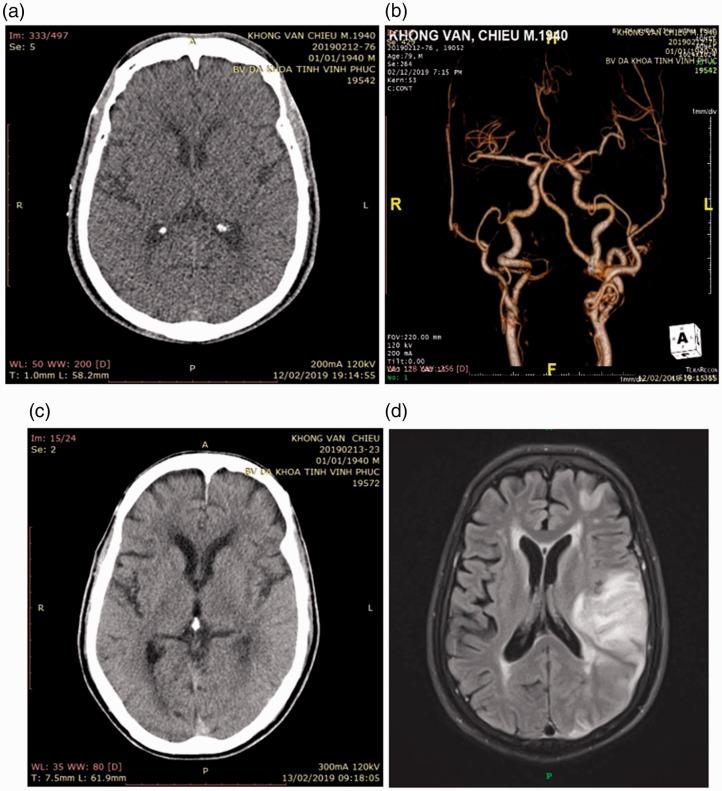

The complication of myocardial infarction after using intravenous recombinant tissue plasminogen activator (rt-PA) in patients with acute ischemic stroke is rare. Several of these cases have been reported in the first 3 hours after infusion of rt-PA. There is controversy on how to manage treatment of the coronary artery, such as intravenous anticoagulants and antiplatelets, at the same time. We introduce a new strategy for treatment of a patient who had ischemic stroke and developed myocardial infarction after intravenous rt-PA therapy. Our case had coronary and cerebral intervention in combination with low-dose intravenous rt-PA. He was successfully treated for coronary occlusion with aspiration thrombectomy.

急性缺血性卒中患者静脉注射重组组织型纤溶酶原激活剂(rt-PA)后发生心肌梗死的并发症较为罕见。其中几例病例已在输注rt-PA后的最初3小时内被报道。对于如何同时处理冠状动脉的治疗,如静脉抗凝和抗血小板治疗,存在争议。我们介绍一种治疗策略,用于一名在静脉注射rt-PA治疗后发生缺血性卒中和心肌梗死的患者。我们的病例采用冠状动脉和脑血管介入联合小剂量静脉rt-PA治疗。他通过血栓抽吸术成功治疗了冠状动脉闭塞。